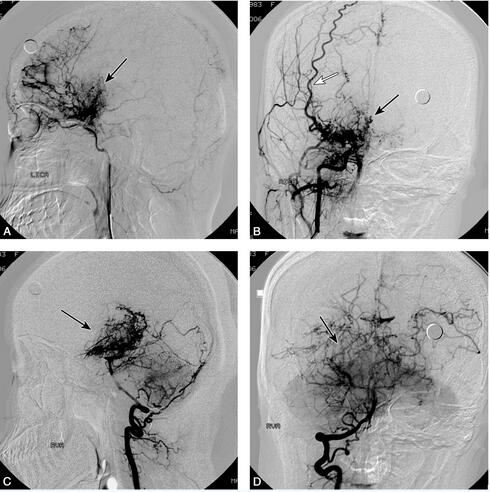

1小时条评论1 病例简介 患儿女,7岁,因反复发作性抽搐9个月,左侧肢体乏力6个月于2007年11月17日入院。患儿于9个月前无明显诱因下被发现突发双眼向左凝视,嘴角向右抽动,伴傻笑,对周围事物无反应,约20秒后自行缓解,之后间断出现3次类似症状。约6个月前,家人发现患儿行走...